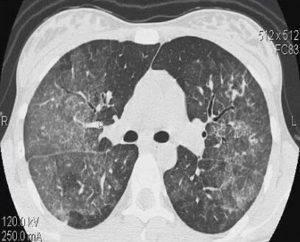

Что показывает компьютерная томография легких

На снимках рентгенолог видит картину вирусного поражения, которая в общих чертах мало отличается от картинки при гриппе. То есть поставить диагноз именно ковидной пневмонии по КТ нельзя.

Характерными признаками действия вируса будут изменения легочных полей в виде очагов (от одиночного до диффузных). Вирусная пневмония выглядит на томографии легких как совокупность типичных изменений.

- «Матовое стекло» — очаг просветления легочного поля из-за снижения воздушности в сочетании воспаления и утолщения межальвеолярных перегородок, заполнения альвеол жидкостью.

- Очаги округлые, могут сливаться между собой и распространяться на большую часть легочного поля. Чаще располагаются на периферии ближе к плевре. Чаще в нижних сегментах.

- «Булыжная мостовая» — утолщение пространства между легочными дольками, за счет чего они выглядят, как разрозненные части дороги.

- Консолидация — уплотнение легочной ткани за счет заполнения альвеол жидкостью.

- Симптом обратного ореола — кольцо консолидации вокруг участка “матового стекла”

- «Воздушная бронхограмма» — просвет бронха, пересекающего участок уплотнения легкого.

- Отмечается чаще двустороннее поражение.

- В отличие от бактериальной пневмонии реже наблюдается усиление легочного рисунка.

Приоритетным экспертным методом диагностики легких и бронхов считается компьютерная томография. Она способна точно воспроизводить детали изображения с охватом широкого спектра плотностей легочной ткани и выявлять начальные признаки морфологической перестройки при опухолевом и некротическом поражении. На первом этапе пациентам с заболеваниями легких обычно назначают выполнить рентгенографию в стандартных проекциях для исключения очаговых и инфильтративных изменений в легких. Если данные рентгеновских снимков носят тревожный характер, для уточнения диагноза, дифференциальной диагностики болезни легких и бронхов вторым шагом врач назначит сделать мультиспиральную компьютерную томографию органов грудной клетки. Она позволяет идентифицировать все мелкие повреждения в легочной ткани, которые имеют особое клиническое значение при выявлении опухолей, пневмонии, астмы, туберкулёза, хронической обструктивной болезни легких. Если данные КТ легких предполагают наличие злокачественного поражения, в качестве дополнительного метода могут назначить пройти МРТ легких с контрастом, чтобы оценить степень инвазии опухоли в ткани средостения и лимфатические узлы.

Компьютерный томограф получает изображения за счет способности рентгеновских лучей проходить сквозь ткани различной плотности с разной скоростью. В легких содержится много воздуха, потому рентгеновские лучи в них не задерживаются, что дает хорошую тканевую контрастность, если в легких и бронха есть новообразования. Поскольку КТ аппарат делать множественные снимки с большой скоростью, он менее чувствителен к артефактам движения. Все это делает КТ более точными информативным методом диагностики легочных заболеваний по сравнению с магнитно-резонансной томографией.